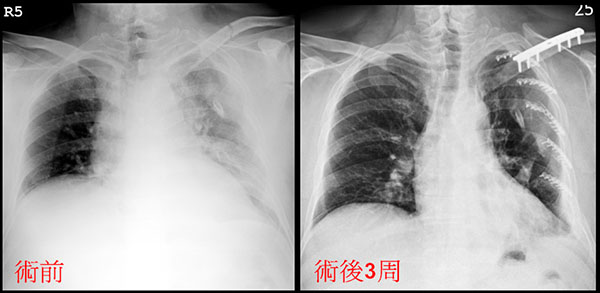

患者術前X光(左)可見左胸因血胸白茫茫一片,術後三周(右)肺功能已逐漸恢復,清晰可見。